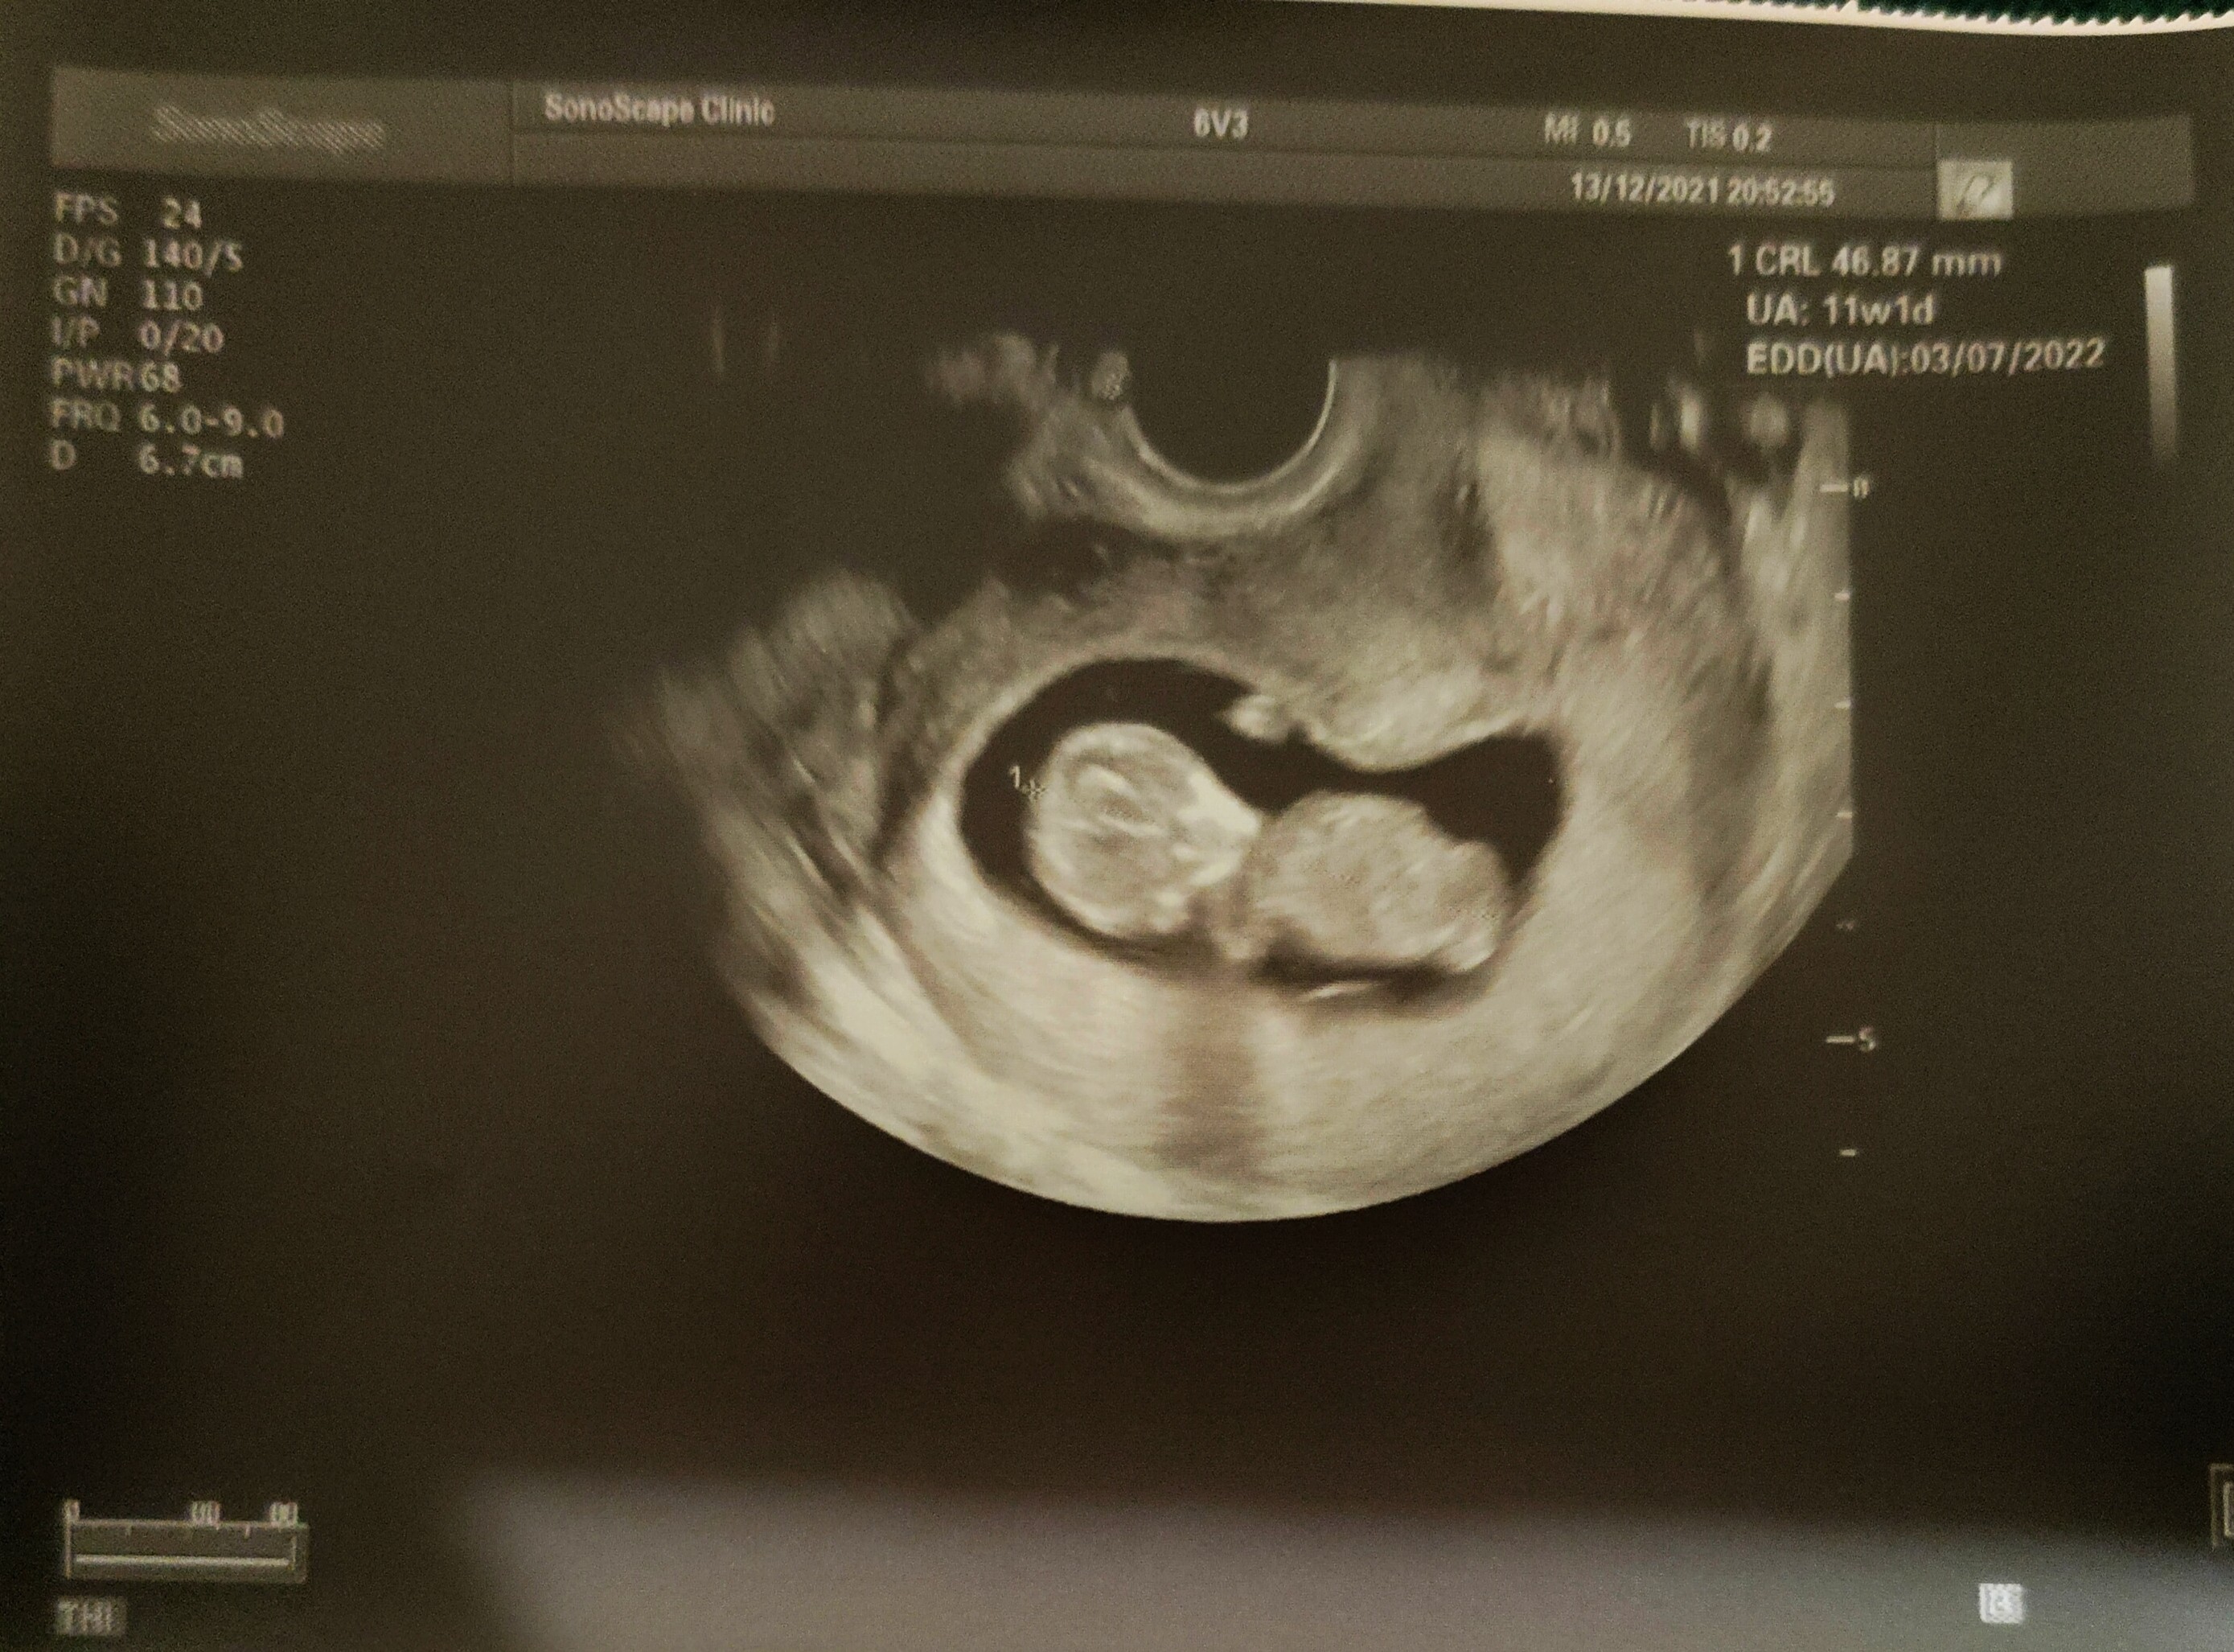

To i ja się podzielę swoją radością ❤️

Zdjęcie z dzisiejszej wizyty.

Dzidziuś 11+1 ma wielkość 46.87 mm

cały i zdrowy, co za ulga i radość 🙂